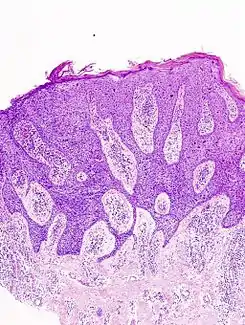

![]() Enfermedad de Bowen, corte histológico visto bajo microscopio. | ||

Histología

La epidermis es remplazada por queratinocitos anormales con desórdenes en la maduración y perdida de polaridad. El estudio histológico de la enfermedad de Bowen muestra una acantosis epidérmica con presencia de queratinocitos atípicos, con alteración de la morfología normal, ausencia de maduración y mitosis que afectan a todo el espesor de la epidermis.